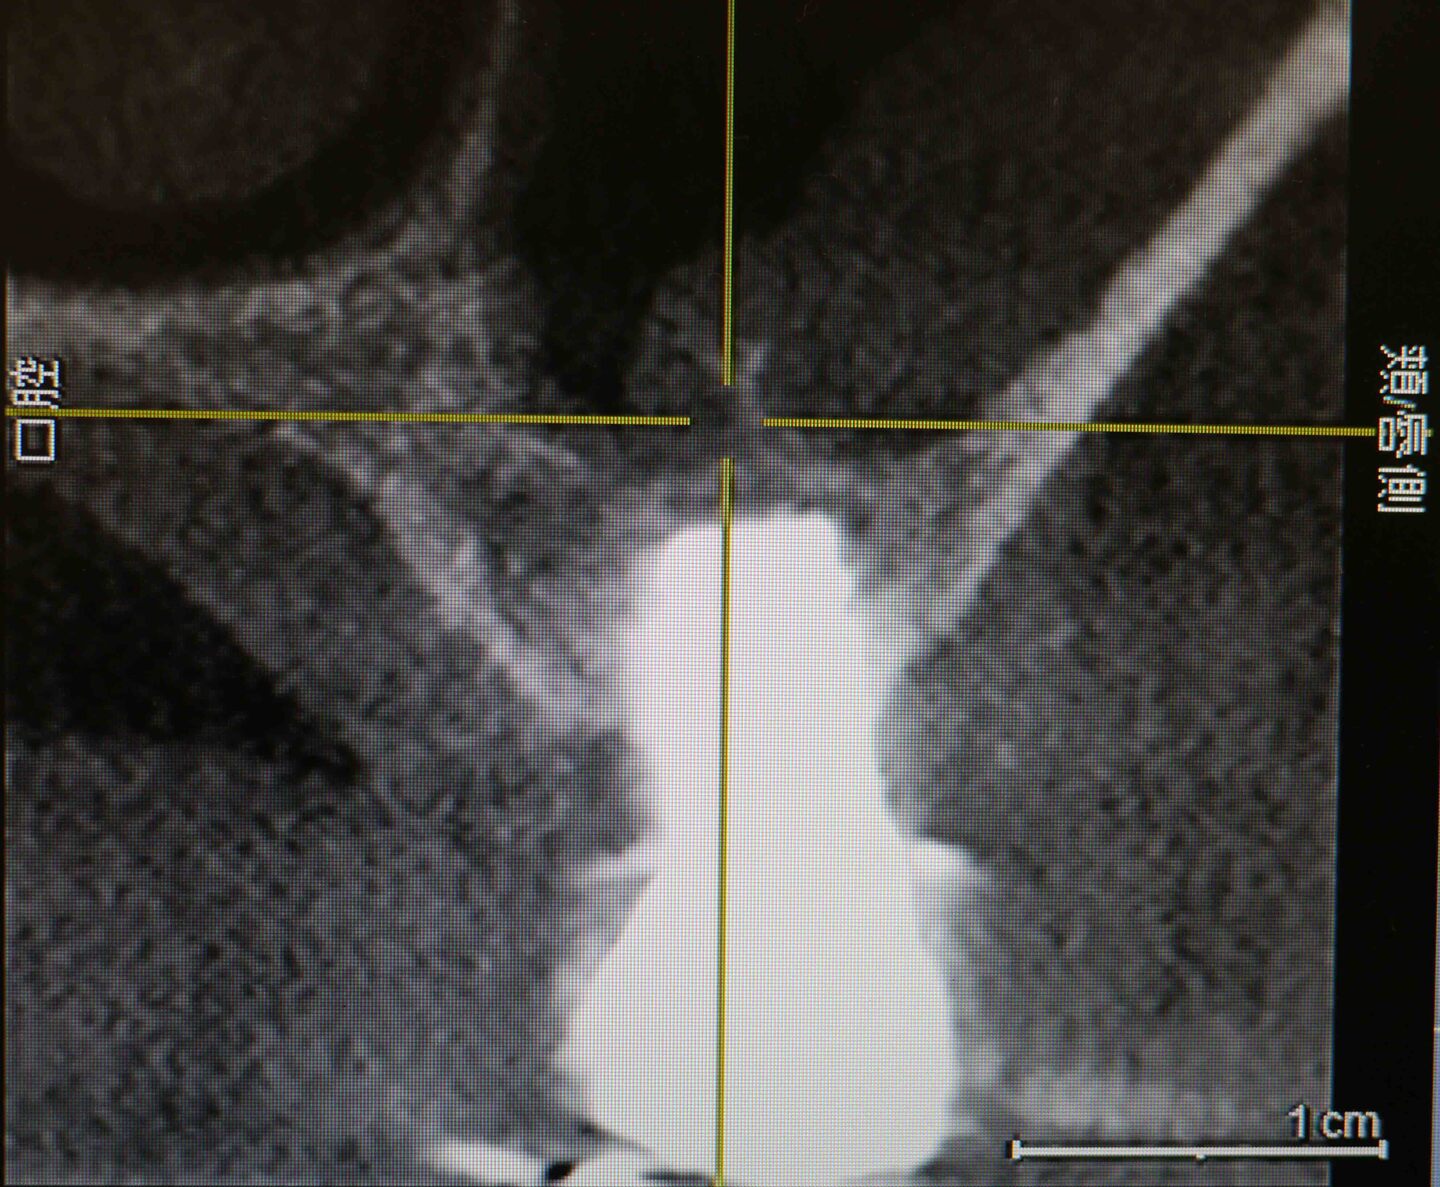

CT画像3

右上6番埋入予定の骨を後側から見たCT